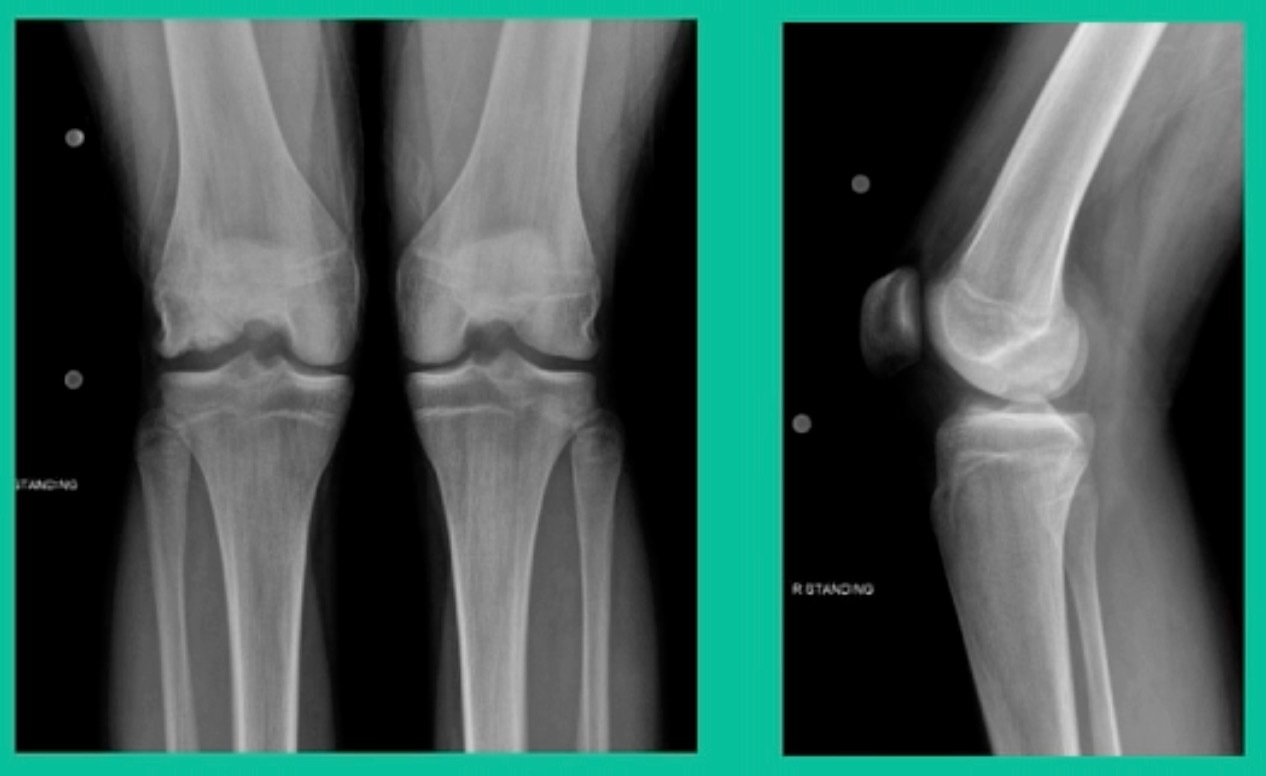

Now a couple of quick cases. This is juvenile OCD. This is the first series of three or four, just juveniles. 14-year-old, intermittent knee pain, lateral femoral condyle OCD (Figure 1).

This is an 11-year-old. Left knee lateral knee pain. Effusions, the same type of classic findings (Figure 3)

Another case example. 14-year-old male tennis player, 10 months of knee pain (Figure 7A).

This is a Trochlear defect (Figure 7B).